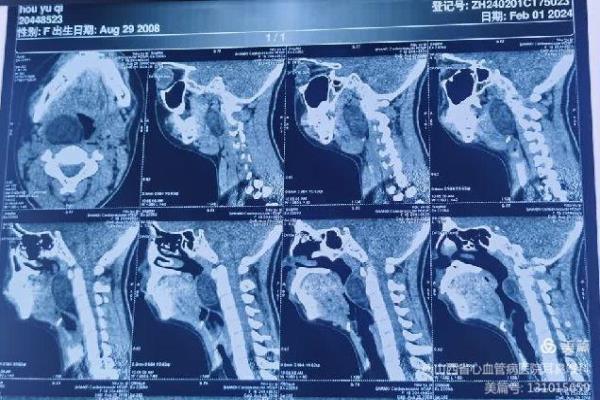

患儿就诊时,自觉偶有憋气及咽痛。张浩杰主任第一时间接诊,经过仔细查体、喉镜和颈部影像学CT与MRI检查后,发现患儿咽腔明显受压,口咽部椎前间隙巨大肿瘤。